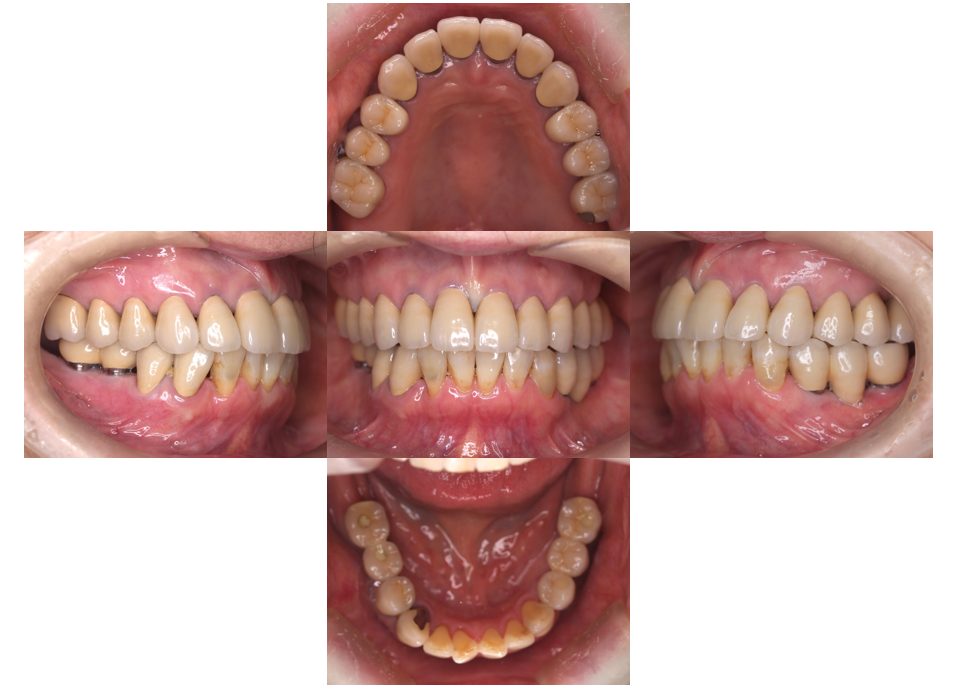

矯正治療・インプラント治療・セラミック治療の症例紹介(三隅歯科クリニック)

三隅 賢祐(三隅歯科クリニック)

症例詳細

| 主訴 | 30代女性 顎関節が痛い。見た目も気になる |

| 治療内容 | 矯正治療を行いました。 |

| 治療費 | 1,700,000円(税込み) |

| 治療期間 | 3年(矯正治療期間 2年半) |

| 治療回数 | 40回 |

| 想定されたリスク | 術前に精密な診査診断とシミュレーションを行い、インプラントを適正なポジションに埋入しておかないと、インプラント自体が矯正治療の邪魔になるリスクがあった。 |